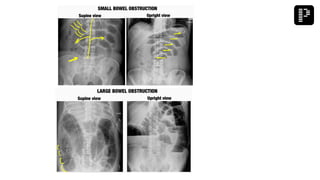

a. Adhesive small bowel obstruction

Q. A multipara patient was brought to the emergency with signs and symptoms of small bowel

obstruction. After resuscitation, X-ray was performed and the findings are given below.

What is the most probable diagnosis?